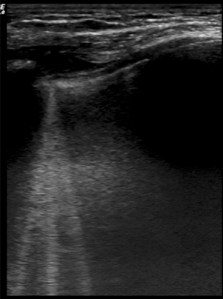

The main findings are the comet tails. They are described as hyperechoic, with a narrow start from the pleuritic line, extending deeply in the lungs. It has been extensively studied for cardiogenic pulmonary edema and it is a sign of fluid accumulation in the lungs.

This is a good example of comet tails:

(Source : Wimalasena et al, Wilderness Environ Med)